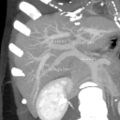

يتميز الكبد من باقي أعضاء البدن بأن ترويته الدموية تتم عن طريقين: طريق وريد الباب الذي يجلب نحو سبعين بالمئة من الدم الذي يدخل إلى الكبد، والشريان الكبدي الذي يجلب قرابة ثلاثين بالمئة من الدم. ينقسم وريد الباب في سرة الكبد إلى فرعين أيمن وأيسر يتفرعان بدورهما إلى فروع أصغر فأصغر تروي قطع الكبد الثمان. كما ينقسم الشريان الكبدي أيضاً في سرة الكبد إلى فرعين أيمن وأيسر يسيران بمحاذاة فروع وريد الباب حتى الشعب الانتهائية. يخرج الدم من الكبد بعد إروائه عن طريق الأوردة الكبدية وعددها ثلاث تصب كلها في الوريد الأجوف السفلي. تجمع الشعيراتُ الصفراوية الصفراءَ التي تفرزها الخلايا الكبدية، وتنضم هذه الشعيرات بعضها إلى بعض لتشكل قنيات صفراوية. تتحد هذه القنيات فيما بينها لتشكل قناتين صفراويتين يمنى ويسرى تلتقيان في سرة الكبد فتؤلفان القناة الكبدية الرئيسة. تسير هذه الأقنية الصفراوية جميعها داخل الكبد وخارجه بمحاذاة وريد الباب والشريان الكبدي وفروعهما.

الجزء المركزي وتوجد به القناة الصفراوية الرئيسية والشريان الكبدي البابي وكذلك الوريد الكبدي البابي وهؤلاء الثلاثة يدخلون في تجويف في مركز الكبد يسمى الهيلم أو الباب الكبدي porta hepatis -Hilum

كلا من الأوعية الثلاثة السابق ذكرهم ينقسم بدوره الى فرعين يمين ويسار حتى يقوموا بتغذية كلا الفصين الأيمن و الأيسر.

وطبقا للتقسيم الفرنسي المستعمل بكثرة في التقسيم الوظيفي للكبد فانه ينقسم الى ثمانية قطاعات صغيرة بناء على الفرع الشرياني الذي يغذي كل منهم في حين أن الفص الذيلي caudate lobe هو قطاع منفصل عن باقي القطاعات حيث أنه يتميز عنهم بأنه يتغذى عل كل من الشريان اليمينى واليساري الكبدي

| Lobe | Couinaud segments |

|---|---|

| Caudate | 1 |

| Left | 2, 3 |

| Quadrate | 4 |

| Right | 5, 6, 7, 8 |